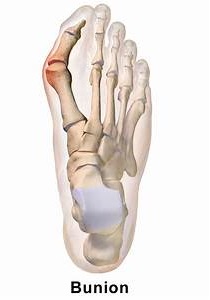

Bunions, referred to in the medical community as Hallux Valgus, are one of the most common forefoot problems. A bunion is a prominent bump on the inside of the foot around the big toe joint. This bump is actually a bone protruding towards the inside of the foot. With the continued movement of the big toe towards the smaller toes, it is common to find the big toe resting under or over the second toe. This causes a common forefoot condition called overlapping toes. Some of the symptoms of bunions include inflammation, swelling, and soreness on the side surface of the big toe. The discomfort commonly causes a patient to walk improperly.

Another type of bunion which some individuals experience is called a Tailor’s Bunion, also known as a Bunionette. This forms on the outside of the foot towards the joint at the little toe. It is a smaller bump that forms due to the little toe moving inwards, towards the big toe.

Bunions are a common problem experienced mostly by women. The deformity can develop from an abnormality in foot function, or arthritis, but is more commonly caused by wearing improper fitting footwear. Tight, narrow dress shoes with a constrictive toe box (toe area) can cause the foot to begin to take the shape of the shoe, leading to the formation of a bunion. Women who have bunions normally wear dress shoes that are too small for their feet. Their toes are squeezed together in their shoes causing the first metatarsal bone to protrude on the side of the foot.

It is important for men and women to realize that wearing dress shoes and boots, which are tapered in the toe area, can cause the bunion to worsen to the point where surgery is necessary.

In the early stages of the formation of a bunion, soaking feet in warm water can provide temporary relief. The best way to alleviate the pain associated with bunions is to wear properly fitting shoes. Shoes designed with a high, wide toe box (toe area) are recommended for people suffering from forefoot disorders, such as bunions. Shoes with rocker soles will unload pressure to the bunion area. Orthotics are also recommended for this condition to provide extra comfort, support, and protection.

Other conservative treatments include using forefoot products designed to accommodate and relieve bunions such as ((bunion shields, bunion night splints, and bunion bandages. These conservative treatments can limit the progression of the bunion formation, relieve pain and provide a healthy environment for the foot.